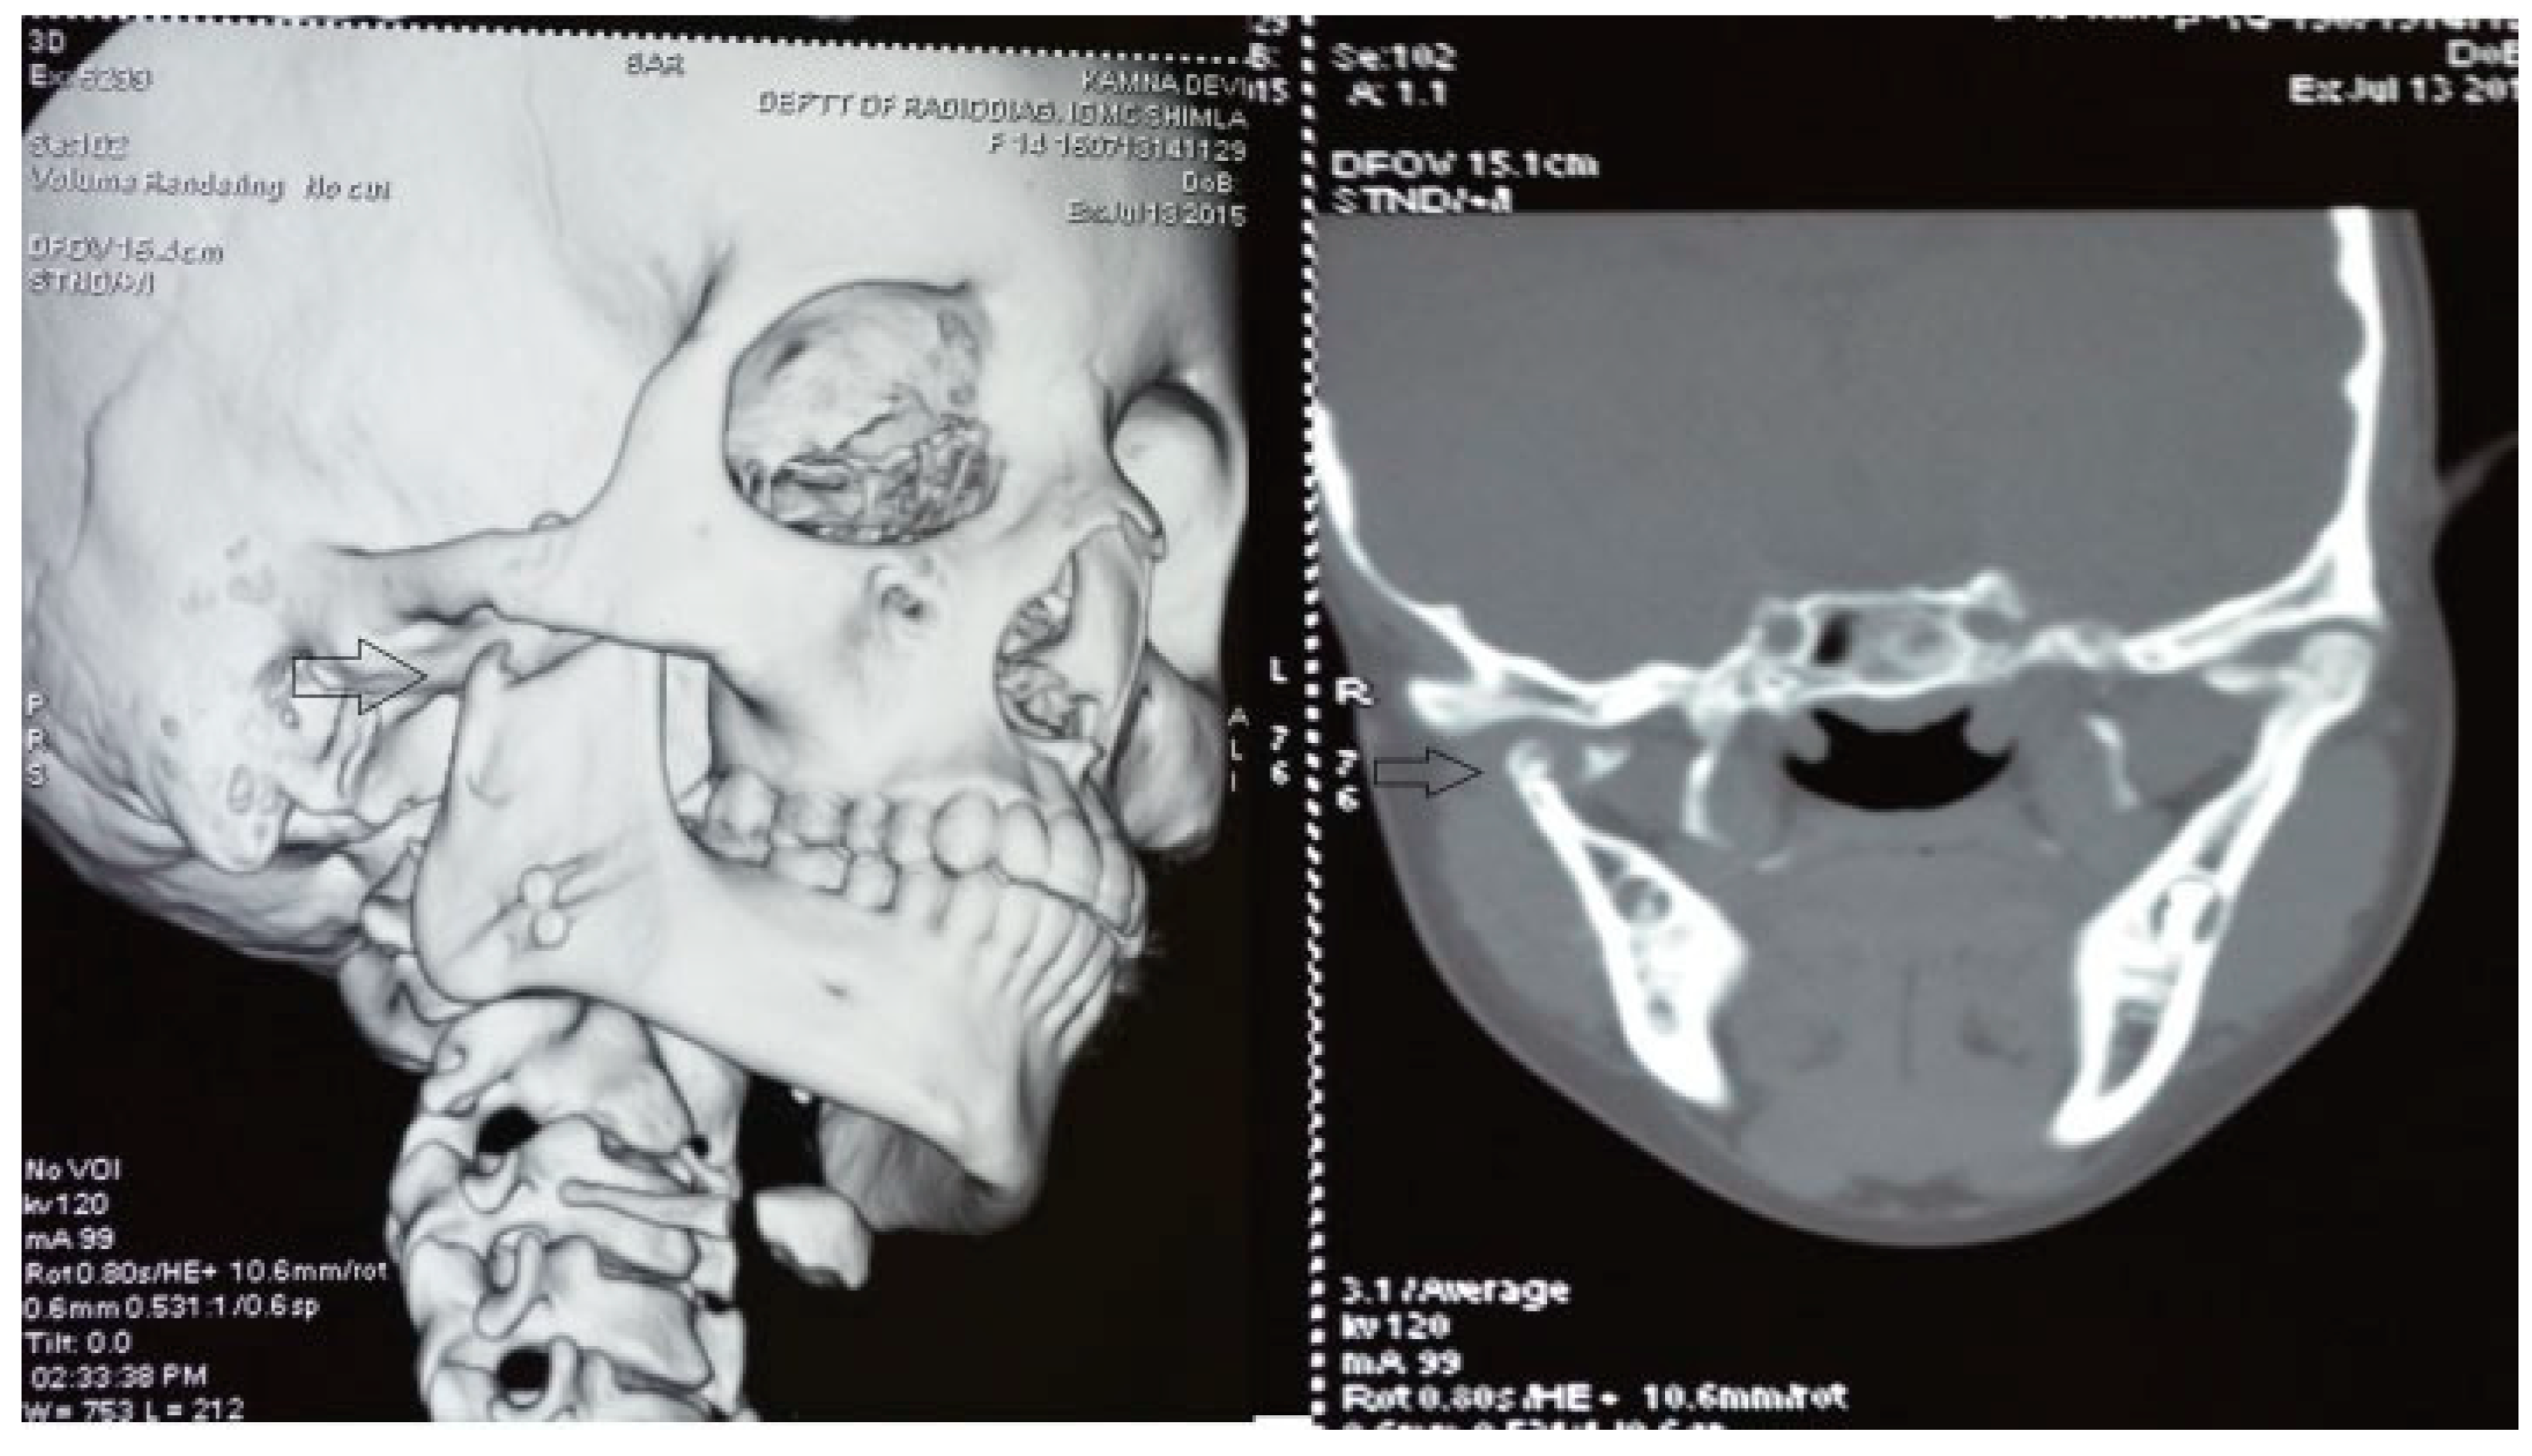

A retrospective study of post–ankylotic TMJ reconstruction of all the patients who underwent surgery for the TMJ ankylosis over a period of 11 years from 2002 to 2013, which were operated by the senior author (Y.B.), was undertaken to evaluate demographics, type of TMJ ankylosis, and modality of post–ankylotic TMJ reconstruction. The following inclusion criteria were considered for enrolling patients in this study: (1) history of traumatic injury to the face or jaws; (2) clinical and radiographic evidence of bony ankylosis at the time of presentation; (3) reconstruction of the TMJ using autogenous or alloplastic material after surgical release of ankylosis. Patients were assessed for (1) maximum interincisal opening pre and post operatively; (2) restored vertical ramal height; (3) occlusion; (4) facial symmetry; and (5) postoperative complications. Radiographic evaluation consisted of both preoperative and postoperative panoramic radiography Orthopentomogram (OPG) (Figure 1 and Figure 2) and CT scans in axial, coronal, and sagittal sections with three-dimensional reconstruction (Figure 3 and Figure 4). Surgical protocol was that the TMJ was approached through the Al-Kayat and Bramley’s incision and at least 2 to 2.5 cm resection of the ankylotic chunk was performed in all our cases. Ipsilateral and contralateral coronoidectomy was performed when required to achieve passive mouth opening. Interpositional arthroplasty was done using various materials such as temporalis fascia, temporalis muscle, and articular disc, whereas joint reconstruction was done using CCG and titanium reconstruction plate with condylar head. Intensive physiotherapy postoperatively was an integral part of protocol.

Figure 4. Postoperative coronal CT and three-dimensional CT scan with temporomandibular joint (TMJ) ankylosis at 6 years of follow-up depicting neocondyle (black arrow) formation (CCG graft with temporalis muscle interpositioning was done with respect to right TMJ).

Temporalis muscle was used in seven patients and temporalis fascia was used in two patients. In our series, using temporalis fascia as an interpositional material in the postoperative MIMO was 37 mm. Temporalis fascia has the disadvantage of being thinner, taut, and nonelastic. Long-term follow-up showed premature contact of teeth on the operated side in both the patients and the ramal height was not maintained. When the temporalis muscle was used as interpositional material, we based our flap on one of the branches of deep temporal arteries to maintain its vascularity and the flap was turned over the zygomatic arch and placed into the glenoid fossa. Temporalis muscle provided us with more bulk to obliterate the joint space and was sandwiched between the chondral end of the CCG and temporal bone. After appropriate positioning has been established, the muscle is sutured in both the anterior and posterior directions. Moreover, there is no hematoma formation and hence had better long-term stability. In patients where temporalis muscle was used, the MIMO was 41 mm and ramal height was maintained in all the cases (Figure 7 and Figure 8). The ramal height was preserved in most of our cases possibly due to unilateral ankylosis with compensation by the contralateral mandibular unit. Management of ankylosis in children can be very challenging and our aim was to correct retrognathia in bilateral cases and reduce the possibility of further asymmetry in unilateral cases. Growth center transplantation using CCGs was done in seven growing children in the 6- to 13-year age group. The uses of this biologically compatible autograft in reconstruction are benefits of growth potential and ability to remodel into a neocondyle with time. Unpredictable growth pattern of the CCG, midline shift, and donor site morbidity are some of the disadvantages of this technique. Overgrowth of the graft has been attributed to the use of a large cartilaginous cap; hence, only 1 to 2 mm cartilaginous cap must be used to avoid such complications [13,14,15]. We assessed the same using panoramic radiographs during follow-ups. The CCGs showed excellent mandibular growth along with complete integration of graft into the recipient site over the passage of time in all seven cases. The CCG was harvested from the sixth rib (contralateral side) using submammary incision and was secured using three 2-mm titanium screws at the recipient site. Due to the close proximity of the chondral cartilage to the base of skull, we routinely interposed temporalis muscle in these patients. The muscle pedicle acted as an artificial disc as well as a barrier between the base of skull and chondral cartilage (Figure 9). Early and vigorous mobilization is important to prevent postoperative adhesions and reankylosis [16]. The postoperative MIMO in seven patients was 41.5 mm. Asymmetry in the form of deviation of chin was found in one patient during long-term follow-up, where CCG overgrowth led to the deviation of the chin to the contralateral side.

The unique ability of the CCG to remodel into neocondyle could be well appreciated on the digital OPG and CT scan of the patient. The length and width of the neocondyle was very much comparable to the length of the condyle on the unaffected side at 6 years follow-up. Thus, the neocondyle formed using the costochondral cartilage was identical to the unaffected mandibular condyle both structurally and functionally. Poor socioeconomic conditions and lack of awareness coupled with poor primary health care facilities lead many of these unfortunate patients to live with this debilitating condition well into adulthood. Five such adult patients with age ranging from 17 to 36 years reported to us for treatment of TMJ ankylosis. In all these patients, ankylotic bony mass extends beyond the boundaries of the joint capsule. Alloplastic reconstruction after the release of ankylosis was our method of treatment, although high cost of condylar prosthesis led us to use 2.4 mm condylar head reconstruction plate along with temporalis muscle interpositioning in these patients. Interpositional grafts may fail to restore the ramal height in bilaterally ankylosed adult patients, so alloplastic condylar reconstruction may become the preferred choice. Advantages of alloplastic TMJ reconstruction are that the physical therapy can begin immediately, there is no need for a secondary donor site, surgery time is decreased, and alloplasts can be constructed in such a way as to mimic the normal anatomic contours of the structures they are to replace [17,18]. Wolford and Karras have suggested autologous fat transplantation as a useful adjunct to prosthetic TMJ reconstruction, as it minimizes the occurrence of excessive joint fibrosis, heterotopic calcification, and improves the range of motion [19]. However, they have categorically stated in their discussion that heterotopic bone formation is seen in multiple operated joints and joints with previously failed alloplastic implants. Another method to combat heterotopic bone formation is the use of 10 Gy of irradiation in five fractionated daily doses in the immediate postoperative period [20]. In our series, none of the patients reported with heterotopic bone formation possibly because they had undergone a single surgical procedure for managing TMJ ankylosis. The risk of fossa perforation could have been taken care by interpositioning of temporalis muscle in all these patients.